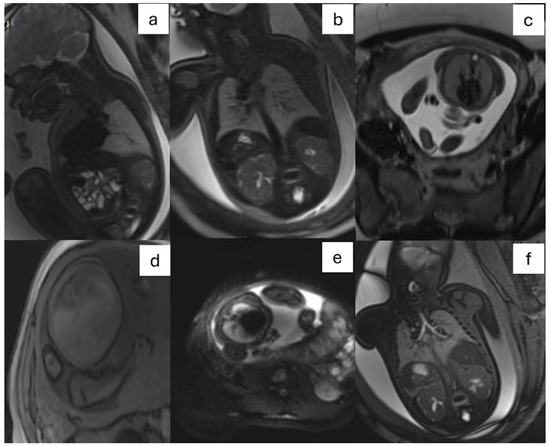

- CDH: It is defined as a herniation of abdominal organs in the thorax through an orifice of the diaphragm caused by delayed or abnormal separation of the thoracic and abdominal compartments (Figure 3).